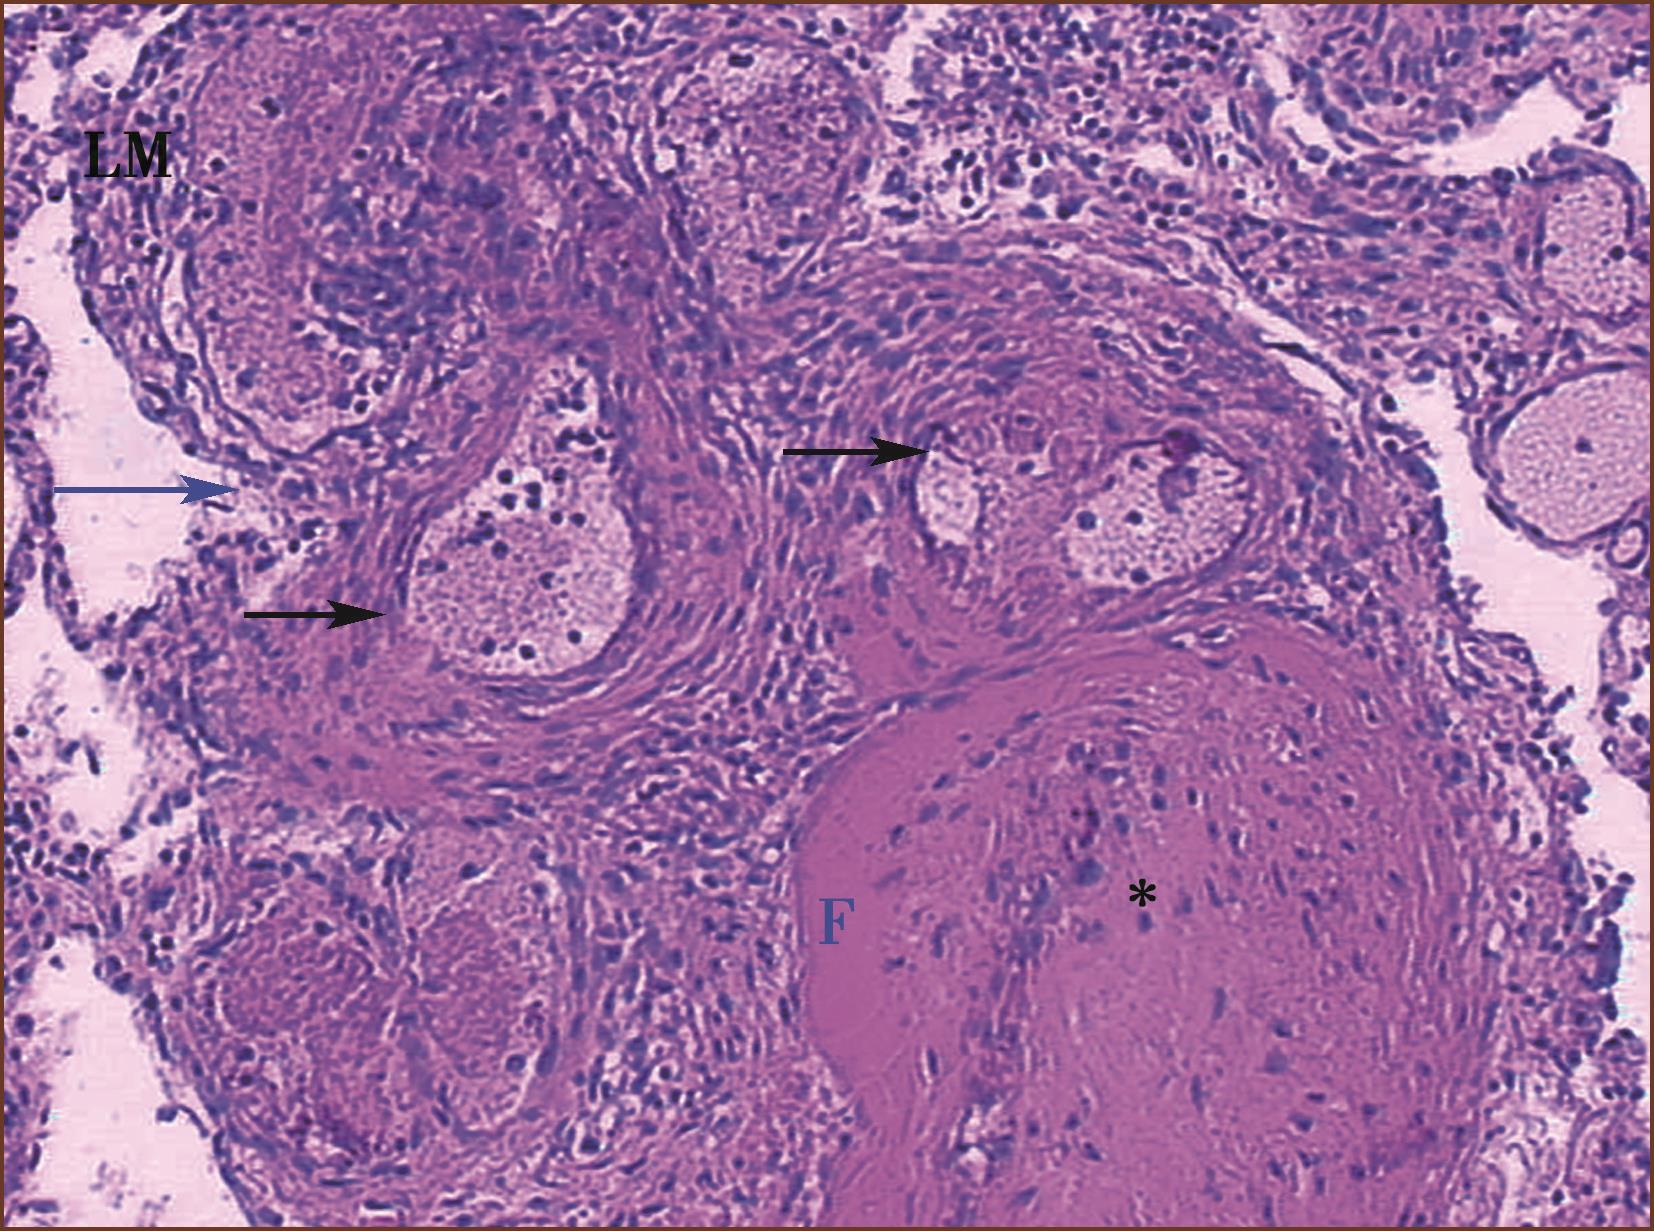

图3-1-14 来自IPAH患者的肺小动脉丛状病变,多个厚薄不一、形状多样的小血管球状及丛状增生,即丛状病变,周围有组织坏死及大量淋巴细胞浸润,为坏死性动脉炎(HE,中倍放大),F:丛状病变

我们在IPAH的尸检肺新鲜标本,从肺门肺动脉注入微粒钡剂,然后取材石蜡制片,显微镜检查,见丛状病变内及其后端血管腔内无钡剂,而其他开放的肺小动脉腔内含有钡剂,说明丛状病变引起了肺小动脉明显阻塞,使钡剂不能通过。

图3-1-16 来自IPAH,图右上方肺小动脉腔呈筛孔状,腔内可见注射的深色钡剂(∗),图中下部的丛状病变裂隙内血管无钡剂,其他薄壁血管为扩张的肺小动脉(HE,高倍放大)